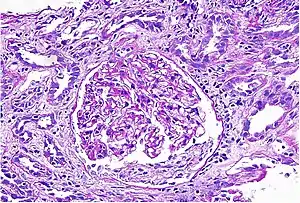

Acute interstitial nephritis on light microscopy

While non-invasive patient evaluation (physical examination, blood and urine testing, imaging studies) can be suggestive, the only way to definitively diagnosis interstitial nephritis is with a tissue diagnosis obtained by kidney biopsy. Pathologic examination will reveal the presence of interstitial edema and inflammatory infiltration with various white blood cells, including neutrophils, eosinophils, and lymphocytes. Generally, blood vessels and glomeruli are not affected. Electron microscopy shows mitochondrial damage in the tubular epithelial cells, vacuoles in the cytoplasm, and enlarged endoplasmic reticulum.[23]